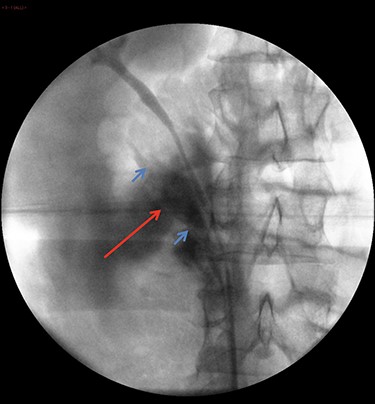

Following discussion with multiple consultant urologists, and in an attempt to avoid a potential laparotomy, a retrograde semi-rigid ureteroscopy was performed to try and stent the transected lower moiety ureter. This showed an intact lumen for ~10-cm proximal to the bifurcation up to an abrupt end in keeping with a transected ureter (Fig. 3). Beyond this, only fat was visualized and the proximal transected end was not seen. Endoscopic retrograde stenting was abandoned and the decision to convert to laparoscopic exploration was made. A 6Ch ureteric catheter was inserted to facilitate identification of the ureter before converting. 3 × 12-mm balloon ports were inserted (open/Hasson technique and direct visualization). A significant retroperitoneal collection was visualized, consistent with urinoma/irrigation fluid. The ascending colon and duodenum were mobilized and the inferior vena cava and gonadal vein were identified. The intact upper moiety ureter was identified. The distal end of the lower moiety was mobilized from the bifurcation and followed proximally to the level of injury where a complete transection was noted. Further dissection towards the kidney revealed the proximal end of the lower moiety. The two ends were spatulated and approximated. The lower moiety ureter was reconstructed using interrupted 4-0 vicryl and a 6Fr/26 cm JJ stent inserted over Sensor® guidewire. The retroperitoneum was washed out, the anastomosis covered with omentum, a 20Fr Robinson’s drain was inserted and port sites were closed.

Retrograde ureteropyelography of right collecting system in theatre. The blue arrows show severed ends of the right inferior collecting system. The red arrow shows the contrast extravasation.